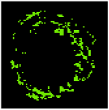

The result of the clustering algorithms will be strongly affected by the presence of outliers that do not belong to any of the clusters [28]. The purpose of outlier detection is to find small groups of pixels that are not similar to the rest of the pixels belonging to the same cluster [72]. Figure 5 illustrates the outliers with dark green, light green, etc., in an NC image. The zoomed area (b) is indicated by the blue box in the original image (a).

Figure 5.

Outliers in an NC image: (a) original image, and (b) zoomed area.

To provide more reliable results, outliers should be removed from the generated clusters. NC and DC images play an important role in TCFA detection; therefore, their outliers are removed for modifying the training set. First, the Euclidian distance between pixels belonging to the NC and its centre are calculated. Then, for each pixel in the NC image, if its distance is greater than the defined threshold value (TNC), then this pixel is an outlier, and its intensity should be replaced with zero. Based on the sub experiments, the value of TNC is changed, and intra-cluster distance (the distance between pixels and the centroid within a cluster) for the NC image are calculated. The value of TNC = 200 gave the best result for the minimum distance between pixels of the NC and its centre. In addition, outliers of DC image are removed in the similar way [45].